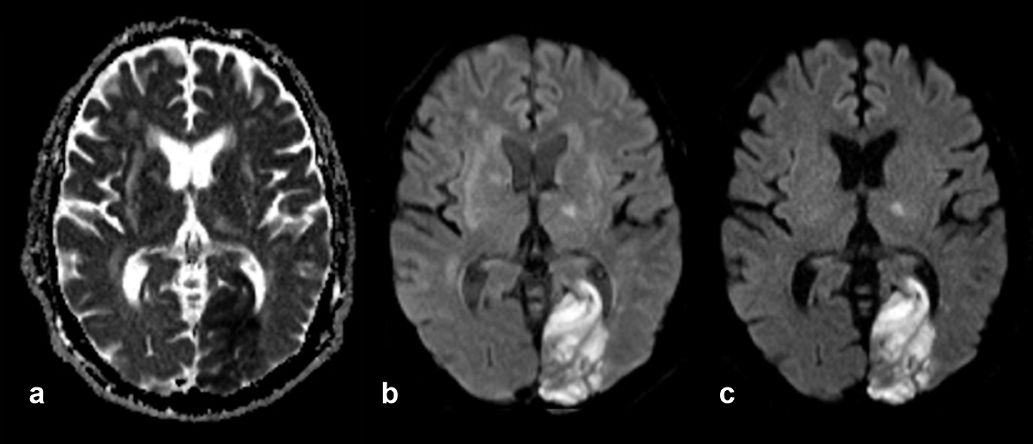

spaceholder redApparent Diffusion Coefficient Imag­ing. The imaging method based on the ap­­pa­rent diffusion coefficient (ADC) serves as graphical illustration of the ability of pro­­tons to diffuse through tissue where they are restricted in their movement by, e.g., cell membranes or increased cellularity — which might be the case in tu­mors. ADC imaging requires at least two data acquisi­tions; its contrast behavior is re­vers­ed: ar­eas of restricted diffusion are dark, those of free diffusion bright (Figure 11-11).

Figura 11-11:

Elderly patient with old and recent brain infarctions. New large infarction in left occipital lobe, also af­fect­ing other parts of the brain.

(a) ADC image, the area of the infarction is dark; (b) diffusion-weighted image, b = 500 s/mm²; (c) dif­fu­sion-weighted image, b = 1000 s/mm². The area of the infarction is bright.